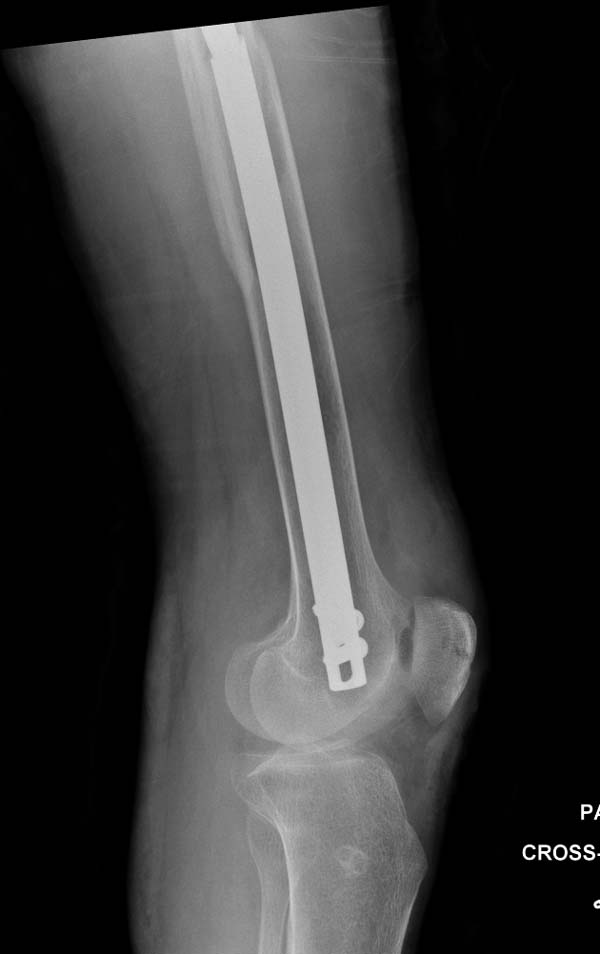

остаться до конца лечения, начал изучать язык... Для облегчения

транспортировки на второй день после поступления правая сторона была

фиксирована ретроградным гвоздем.

Гвоздь из ретроградного гвоздя DePuy в 15 мм получился немного тоньше,

чем у Российских коллег.

Операция не обошлась без казуса, при подготовке гвоздя произошла ошибка

в расчете. Пришлось коррегигировать по ходу операции, где длинный

дистальный отдел гвоздя срезали во время операции.

А так вроде первый американский опыт прошел удачно. У больного низкий

гемоглобин, который подправили во время операции переливанием крови.

надеюсь, контрагированные мышцы сохранит длину конечности. Контрольный

снимок показал устойчивую фиксацию.